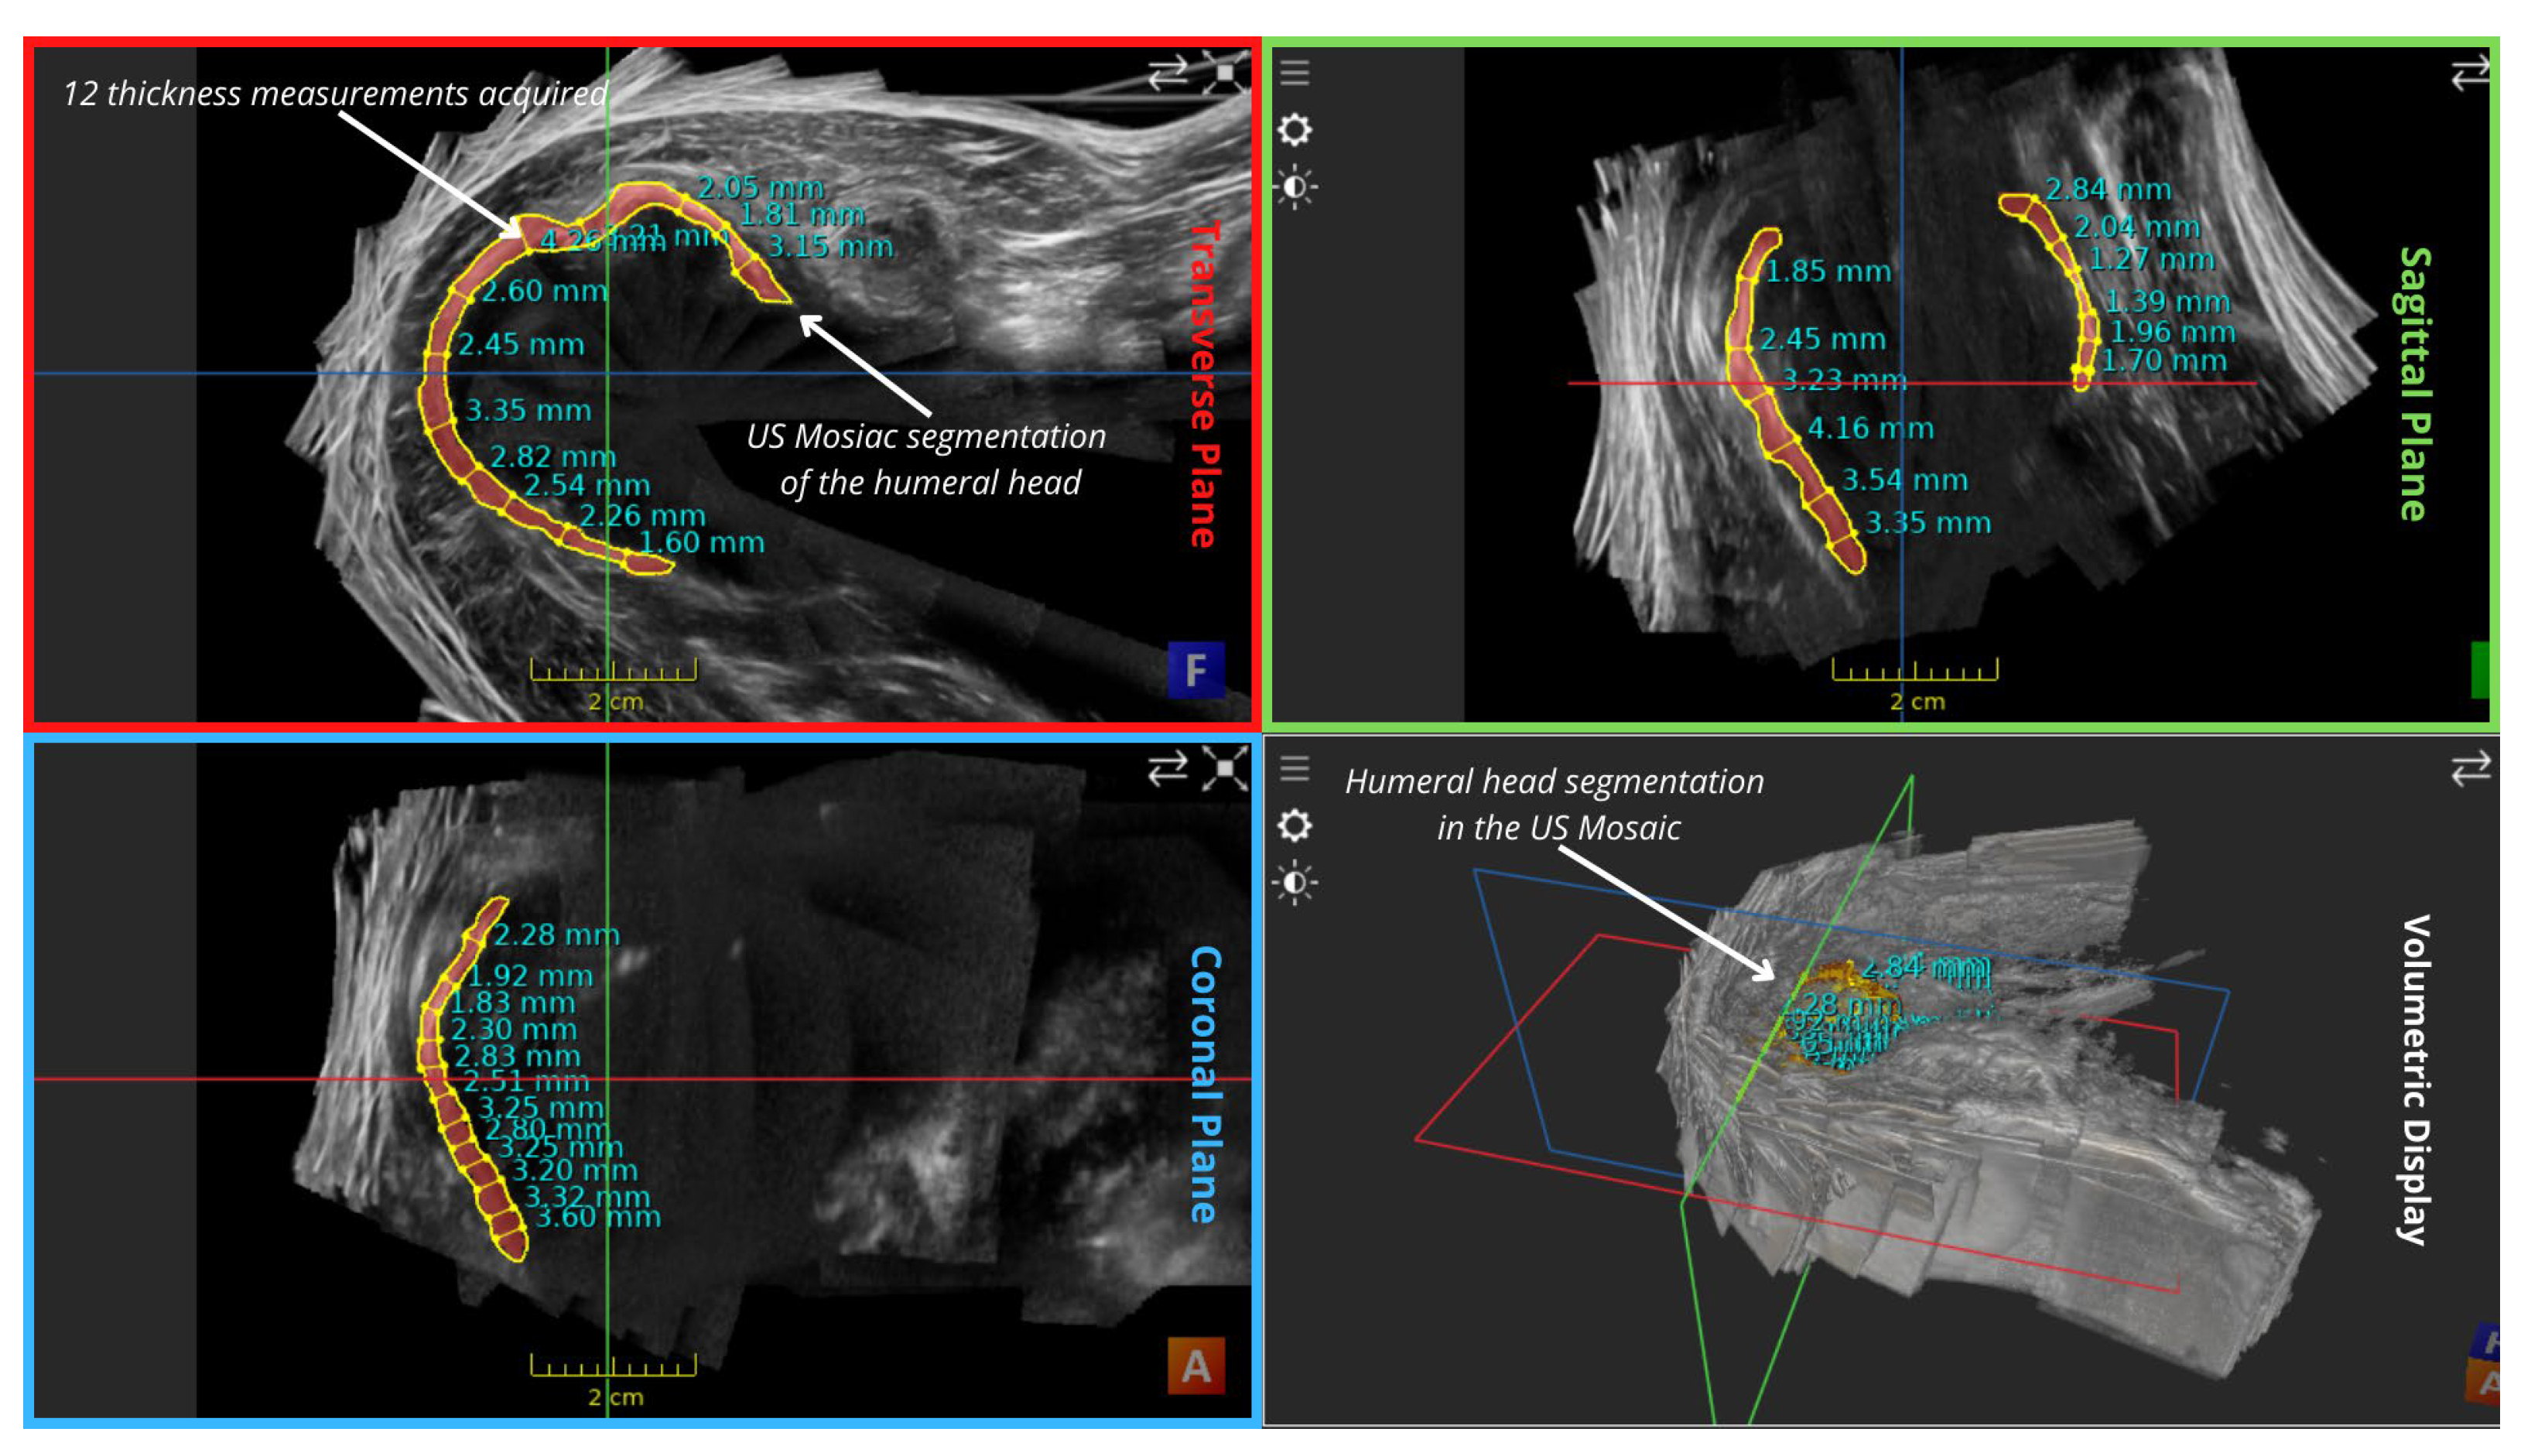

| Mean Values (mm) | Transverse Plane | Sagittal Plane | Coronal Plane | Overall |

|---|---|---|---|---|

| Thickness in mosaic | 2.675 | 2.481666667 | 2.755 | 2.637222 |

| Thickness in a single volume | 1.686666667 | 1.758333333 | 2.52 | 1.988333 |

| Reconstruction Error (Thickness) | 0.988333333 | 0.723333333 | 0.235 | 0.648889 |